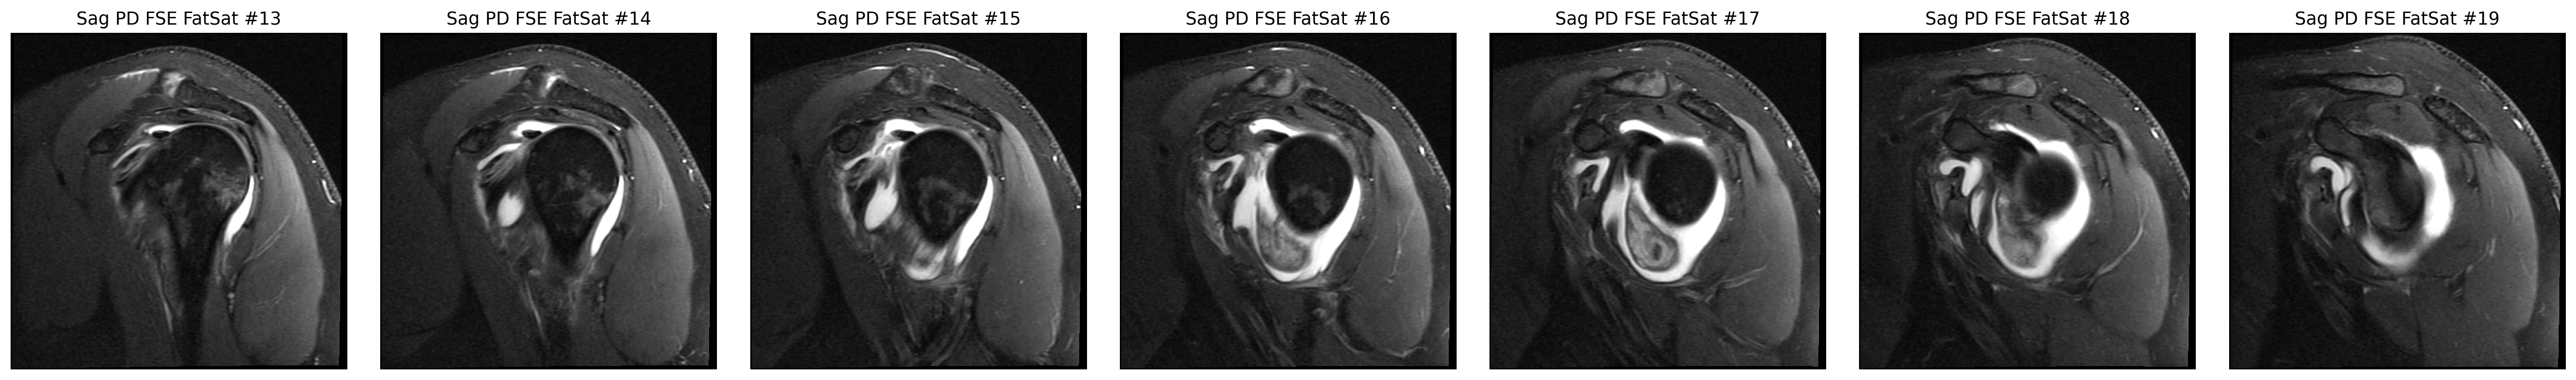

The cuff finding was checked in coronal and sagittal views, while the labrum was reviewed on axial arthrogram slices.

The strongest image-only read is a smaller tear or split on the joint-facing side of the supraspinatus tendon where it attaches to bone.

The space that cushions the tendon looks irritated and fluid-filled, which commonly travels with cuff problems.